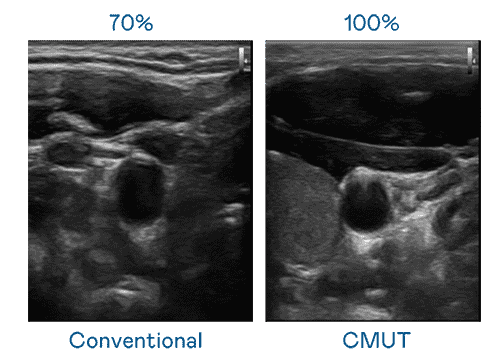

CMUT 技术是一种用电容式微机电元件来产生超音波讯号的技术。。。与传统 PZT 压电式技术相比,,,,CMUT 频宽增加 30%,,,,更宽频的超音波讯号让影像解析度大幅提升,,,是实现高影像品质医疗超音波扫描、、促进精准医疗发展的关键技术。。。

大频宽带来超清晰影像

超音波影像的解析度高低,,,首先取决于探头能发出的讯号频宽。。。。至成国际 CMUT 可提供高清晰的超音波讯号,,,,提供高频宽、、、、高灵敏度、、影像纹理细节更高的超音波影像,,,协助医护人员缩短影像判读时间及利用精准的医疗影像进行诊断。。。。